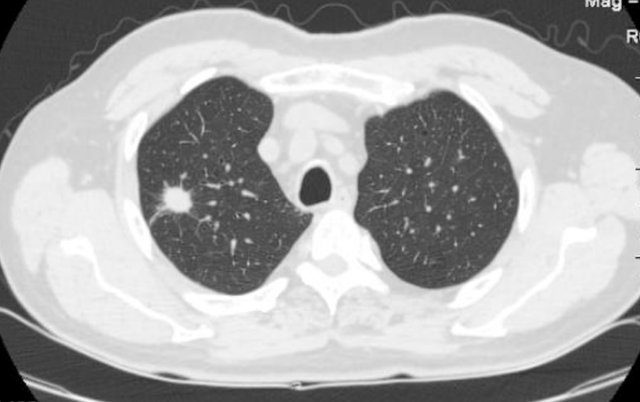

其中的孤立性肺结节是比较常见的一种,它主要是指单一、边界清楚、影像不透明、直径小于或等于3cm、周围为含气肺组织所包绕的肺部结节病变,无肺不张、肺门增大或胸腔积液的表现。

孤立性肺结节为常见病,常见原因为肿瘤、感染性肉芽肿、先天性病变等原因,良性结节无症状可不进行治疗,恶性结节主要治疗方法为手术切除或放化疗,良性结节预后良好,恶性结节预后稍差。